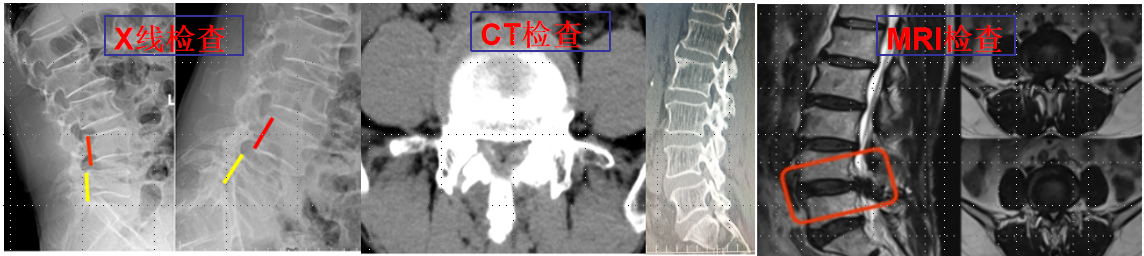

基本情況重慶醫科大學附屬璧山醫院(重慶市璧山區人民醫院)骨科(脊柱外科)于2025年9月1日正式成立,是集醫療、教學和科研為一體的臨床學科,設有脊柱專科門診、住院病區兩個功能區域。有編制床位30張,科室實際開放床位35張。科室硬件設施齊備,技術力量雄厚,人才結構合理,擁有一批技術力量強,醫療服務好的高素質技術人才。

①脊柱導航技術:為脊柱微創技術更加精準高效的操作提供保障,從而減少患者創傷和痛苦。

②椎間孔鏡技術:科室常規熟練開展椎間孔鏡技術治療頸、胸、腰椎椎間盤突出癥、椎管狹窄癥、椎管黃韌帶骨化等。

③UBE技術(單側雙通道內鏡技術):率先在重慶市內開展此項技術,用于治療腰椎間盤突出癥、腰椎管狹窄癥、腰椎滑脫(失穩)癥及頸椎病、頸椎管狹窄癥等。

MIS-TLIF技術(微創通道下腰椎融合技術)。

椎體成形術(PVP)及椎體后凸成形術(PKP):熟練開展此項技術治療老年骨質疏松性胸腰椎壓縮性骨折,此項技術具有創傷小、恢復快、住院時間短等優點,可以快速緩解患者胸腰背部疼痛,提高患者生活質量。

頸、胸、腰椎骨折伴或不伴有脊髓損傷的前后路減壓、融合、固定技術。

經皮微創椎弓根螺釘固定技術。

頸椎病經前路椎間盤切除(椎體次全切除)椎管減壓植骨融合固定術(ACDF/ACCF)。

脊柱感染(包括結核)的保守和手術治療。

脊柱畸形的早期評估及手術治療。

?脊柱腫瘤的外科治療等。